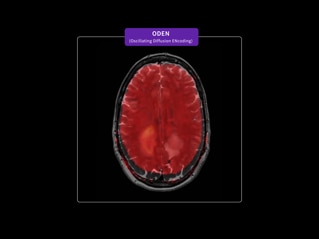

Our goal is to help you personalize cancer diagnosis, radiation therapy planning and treatment assessment for every patient. To achieve this, we can provide advanced functional and metabolic imaging information with SIGNA™ PET/MR AIR™⁵ and ODEN* (Oscillating Diffusion Encoding). Our AIR™ RT Suite solution is easy to set up and helps ensure the proper positioning of each patient. And the 32-channel AIR™ Open Coils provide patient comfort while delivering a high signal-to-noise ratio.

*SIGNA™ MAGNUS and ODEN are 510(k) cleared with the FDA. Not yet CE Marked. Not available for sale in all regions.